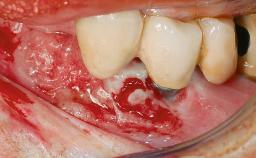

A 77-year-old male patient was referred for the management of frequent and repeated acrylic fracture of his existing mandibular fixed full-arch implant-supported metal/acrylic prosthesis. He also complained about softtissue soreness and the lack of retention and stability of his maxillary removable partial metal/acrylic prosthesis. Both prostheses had been delivered two years previously as part of his full-mouth rehabilitation (caries, tooth wear, tooth fracture). His medical history revealed high blood pressure, controlled with the use of antihypertensive medication.

Defining Characteristics Fully edentulous lower jaw to be rehabilitated with two or more implants

Modality > 4 implants, extending to mental nerve region